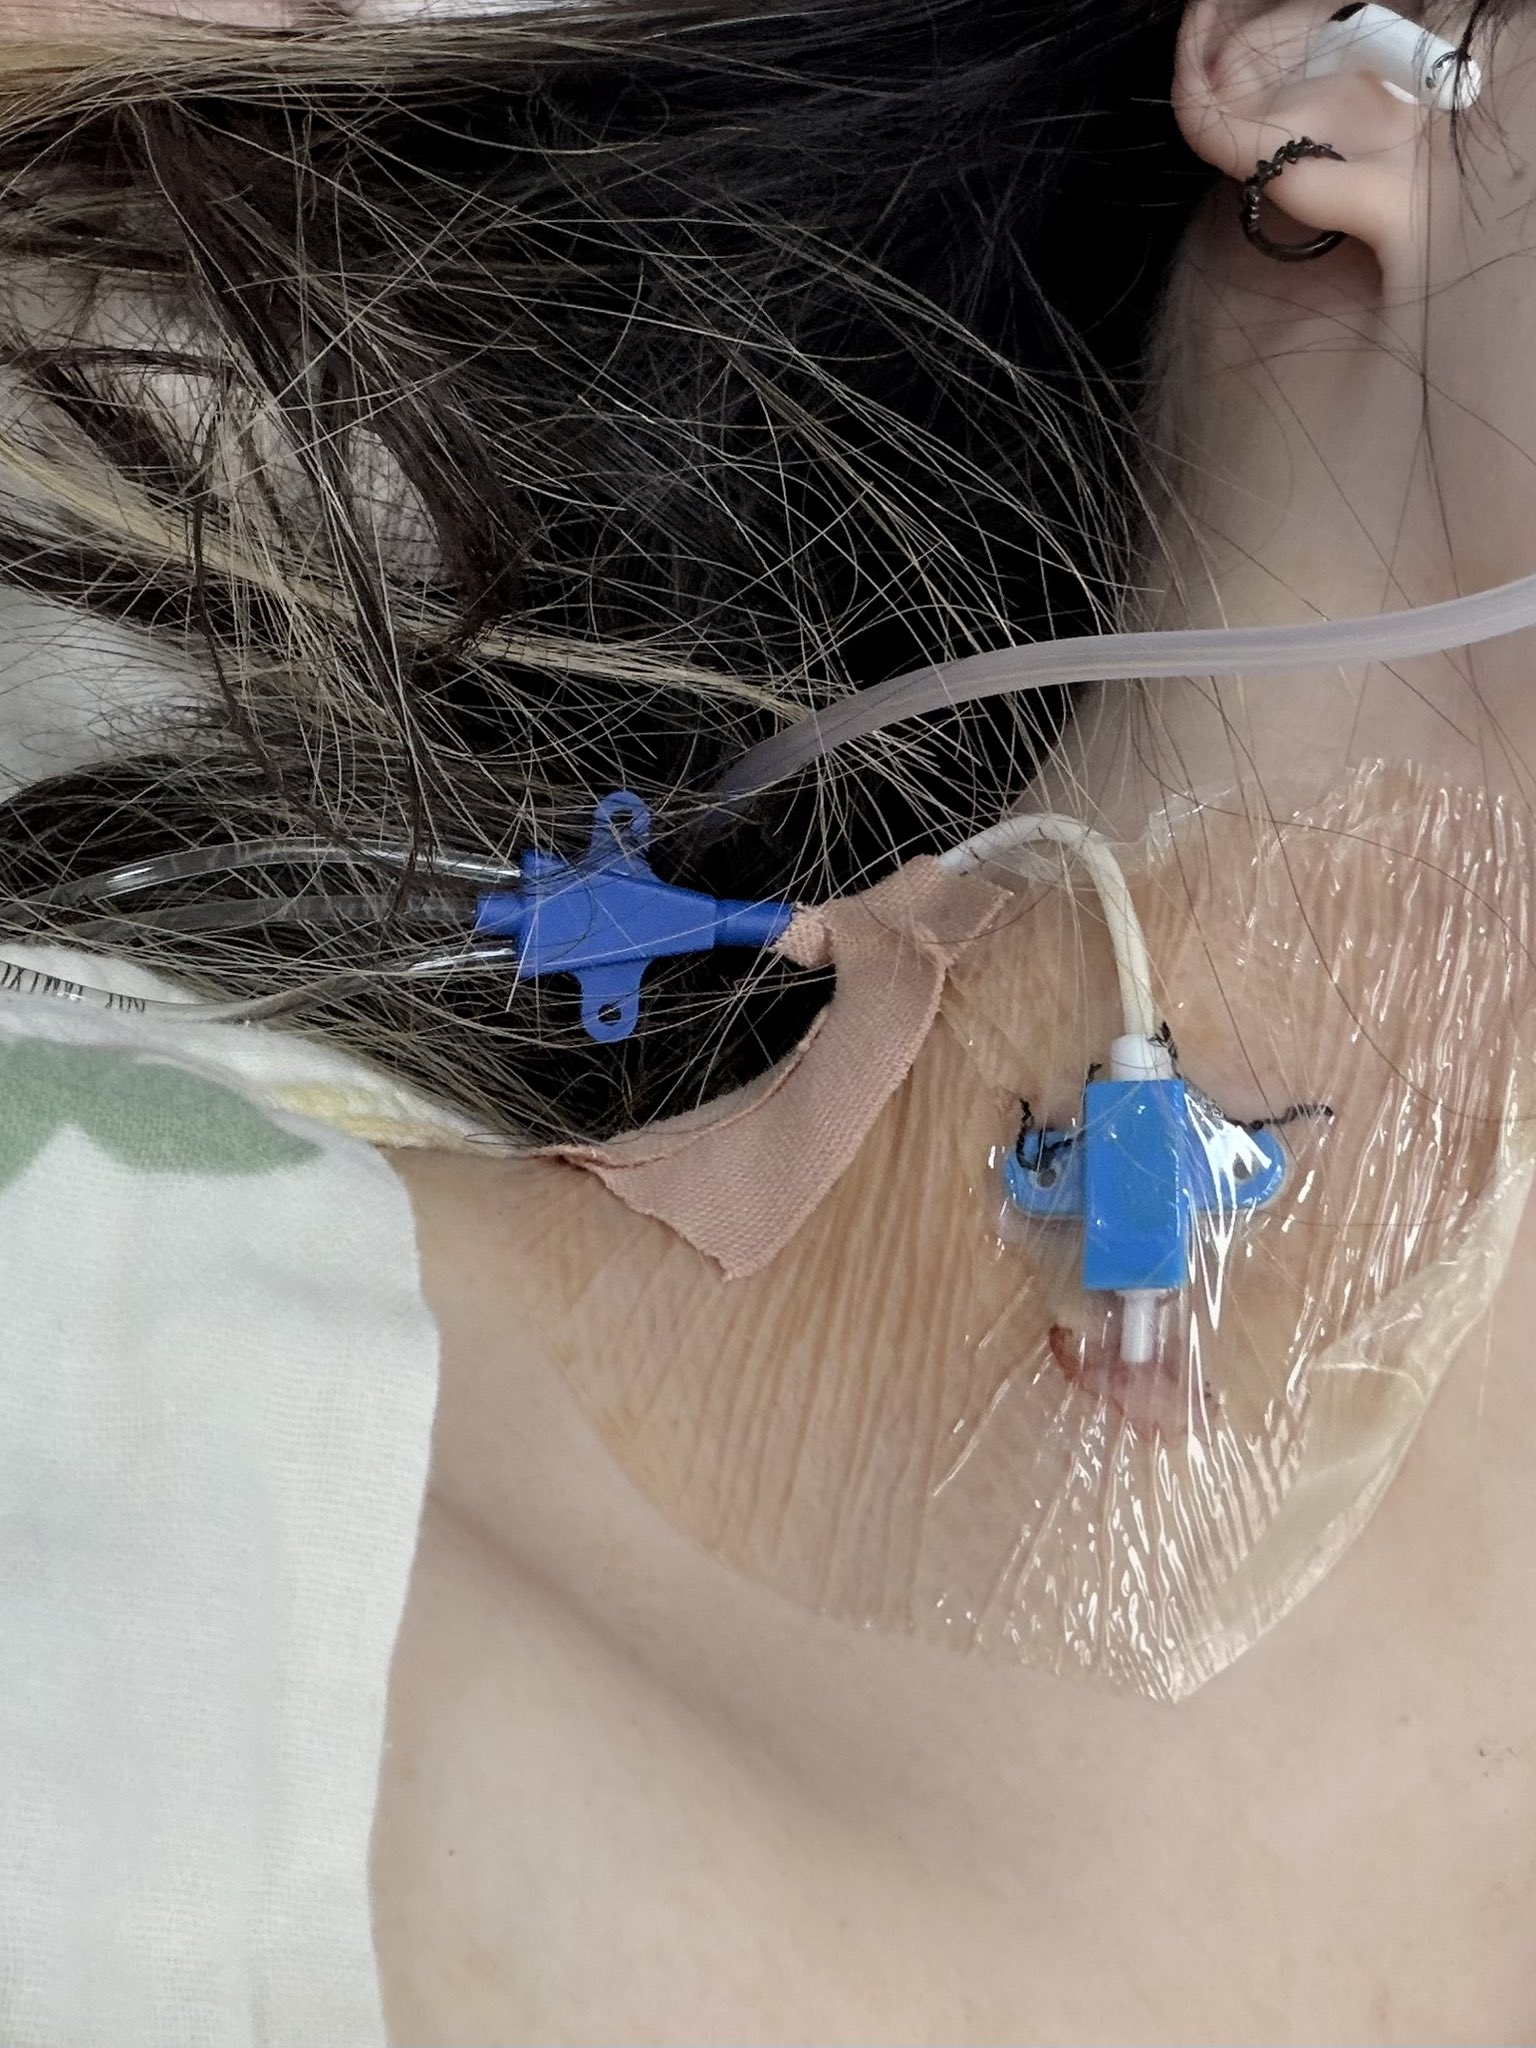

中心静脉置管留下了一片可观的淤青……而且主要分布在固定的小翅膀那里(?)

拔管的时候拆线包里的剪刀太粗了,总之一通我看不到的操作然后有一股拉扯力和剧痛和我的一声惨叫。。不知道和这有没有关系。

最后摇人拿来了手术刀片在我脖子上比划比划,然后看到拿出一根很长的管子x https://t.co/6ZTBuBOWJe

炽烈已极 @AnIncandescence消毒的时候这么痛我才看清底下那里不是胶带留的胶而是伤痕。。这里医生感觉操作好不规范啊,而且从我醒了之后就在说我左腿膝盖以下没知觉到出院也没管我没做任何检查,胸痛也没管就说痒痒,嗯没死就行是吧 https://t.co/jzkLbc6AOx